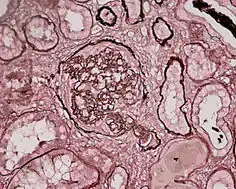

За патоморфологічними ознаками виділяють декілька морфологічних форм гломерулонефритів[8]:

| Морфологічний тип | Характеристика | Частота |

|---|---|---|

| ГН з мінімальними змінами клубочків | Світлова мікроскопія практично не показує змін; електронна мікроскопія показує зливання малих відростків подоцитів | близько 80 % випадків нефротичного синдрому в дітей |

| Ендокапілярний дифузний проліферативний ГН | Є морфологічним еквівалентом гострого постстрептококового ГН; збільшені малокровні клубочки; обтічний інтерстицій інфільтрований полімофноядерними лейкоцитами; зміна структури клубочкового капіляра не відмічається | виникає у більшості випадків гострих постстрептококових ГН |

| ГН з «півмісяцями» | У просторі Боумана позакапілярно проліферуються клітини, що призводить до утворення «півмісяців» (серпів) у 60-100 % клубочків, які стискають його іззовні, та спадання капілярних петель; ниркова тканина заміщається фіброзною при термінальній фазі | виникає при більшості підгострих гломерулонефритів |

| Мезангіопроліферативний | Мезангій розширений унаслідок проліферації мезангіальних клітин та інфільтрації моноцитами | близько 5-10 % усіх випадків ідіопатичного нефротичного синдрому |

| Мезангіокапілярний | Дифузне розширення клубочкових базальних мембран, проліферація мезангіальних клітин, збільшення мезангіального матриксу | близько 15 % випадків ідіопатичного нефротичного синдрому в дітей і 30 % у дорослих |

| Мембранозний ГН | Дифузне потовщення ГБМ капіляру | близько 30-40 % випадків нефротичного синдрому в дорослих і 5 % у дітей |

| Фокально-сегментарний гломерулосклероз | Ураження окремих клубочків, у яких склерозується частина петель; склерозовані петлі зростаються з грубою і склерозованою капсулою Боумана, що надалі призводить до гломерулосклерозу | близько 15-25 % випадків нефротичного синдрому в дорослих і 10-15 % у дітей |

| Фібропластичний ГН | Останній етап морфологічної еволюції гломерулонефриту; спостерігається дифузний склероз структур нефрона | виникає внаслідок більшості гломерулонефритів |